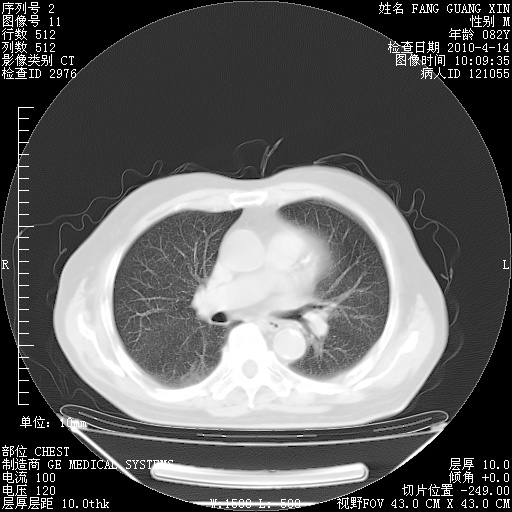

肺部CT平扫未见异常。

4月14日肺部CT